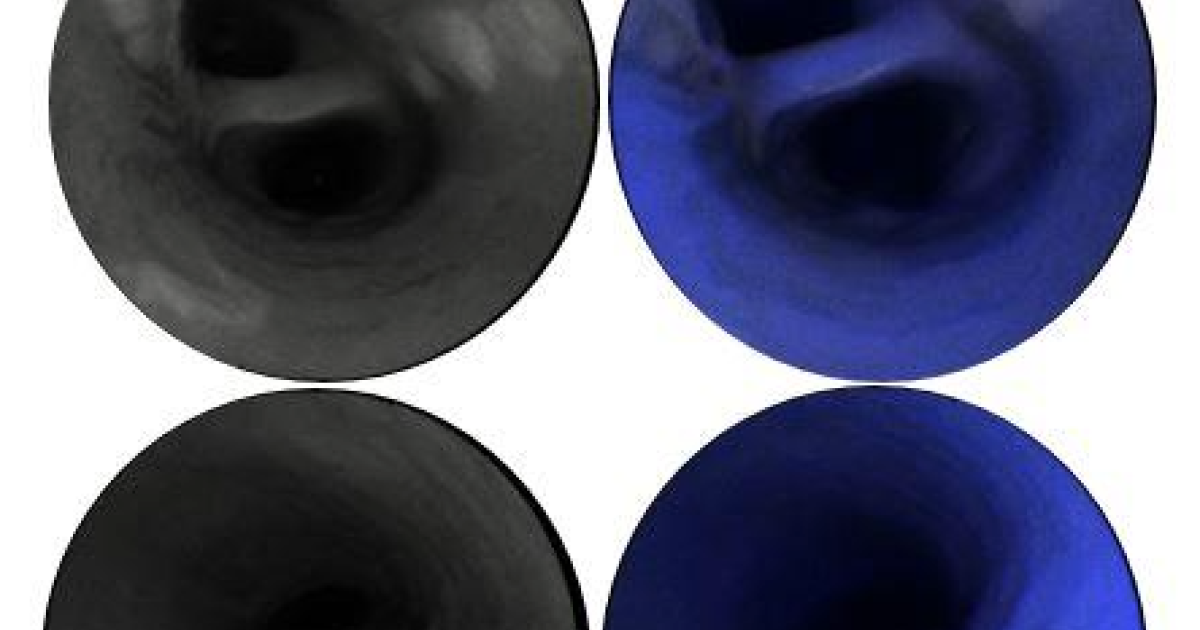

The technology, when you think about it, is quite amazing. Once the micro-camera is inserted, laser beams illuminate the area and high resolution images are gathered, then reassembled, and then returned along the outside of the device – in real time – for doctors to view. (Image courtesy of Michigan Medicine)

"This system consists of an ultrathin, highly flexible catheter that scans blue, green and red laser beams ... in a spiral pattern on the tissue surface, and that collects reflectance and fluorescence," according to the paper. By combining those two pieces, "we were able to co-generate endoscopic videos ... of healthy and diseased arteries."